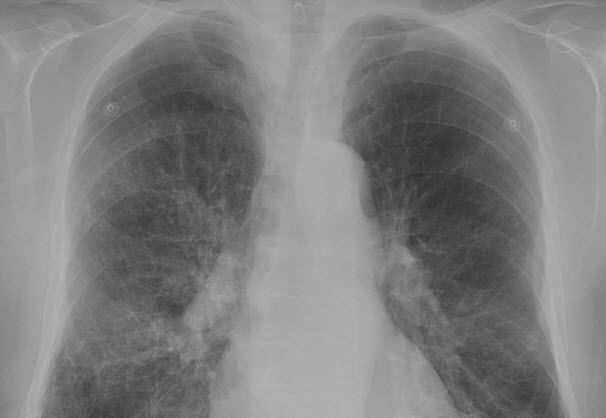

COPD uit basisverzekering vanaf 2019 De ministerraad heeft vandaag besloten dat verzekerden de eerste 20 behandelingen voor fysiotherapie bij COPD per 1 januari 2019 uit de basisverzekering vergoed krijgen. Besluit Dit besluit betekent een aanzienlijke verbetering van...